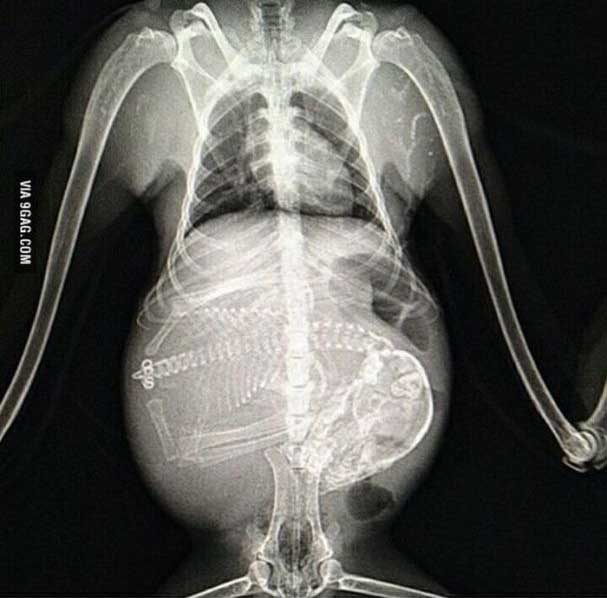

妊娠した様々な動物たちをレントゲン(X線)写真で見てみたギャラリー。サメ、ネズミ、犬、猫など。一度に複数の子供を出産する犬や猫などは特に怖い事に…。

6. ネコ